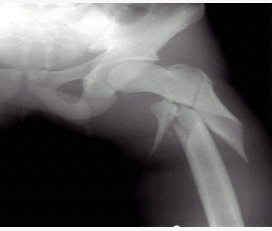

- 单项选择题病史:男性,35岁,外伤30分钟。诊断:()

- C